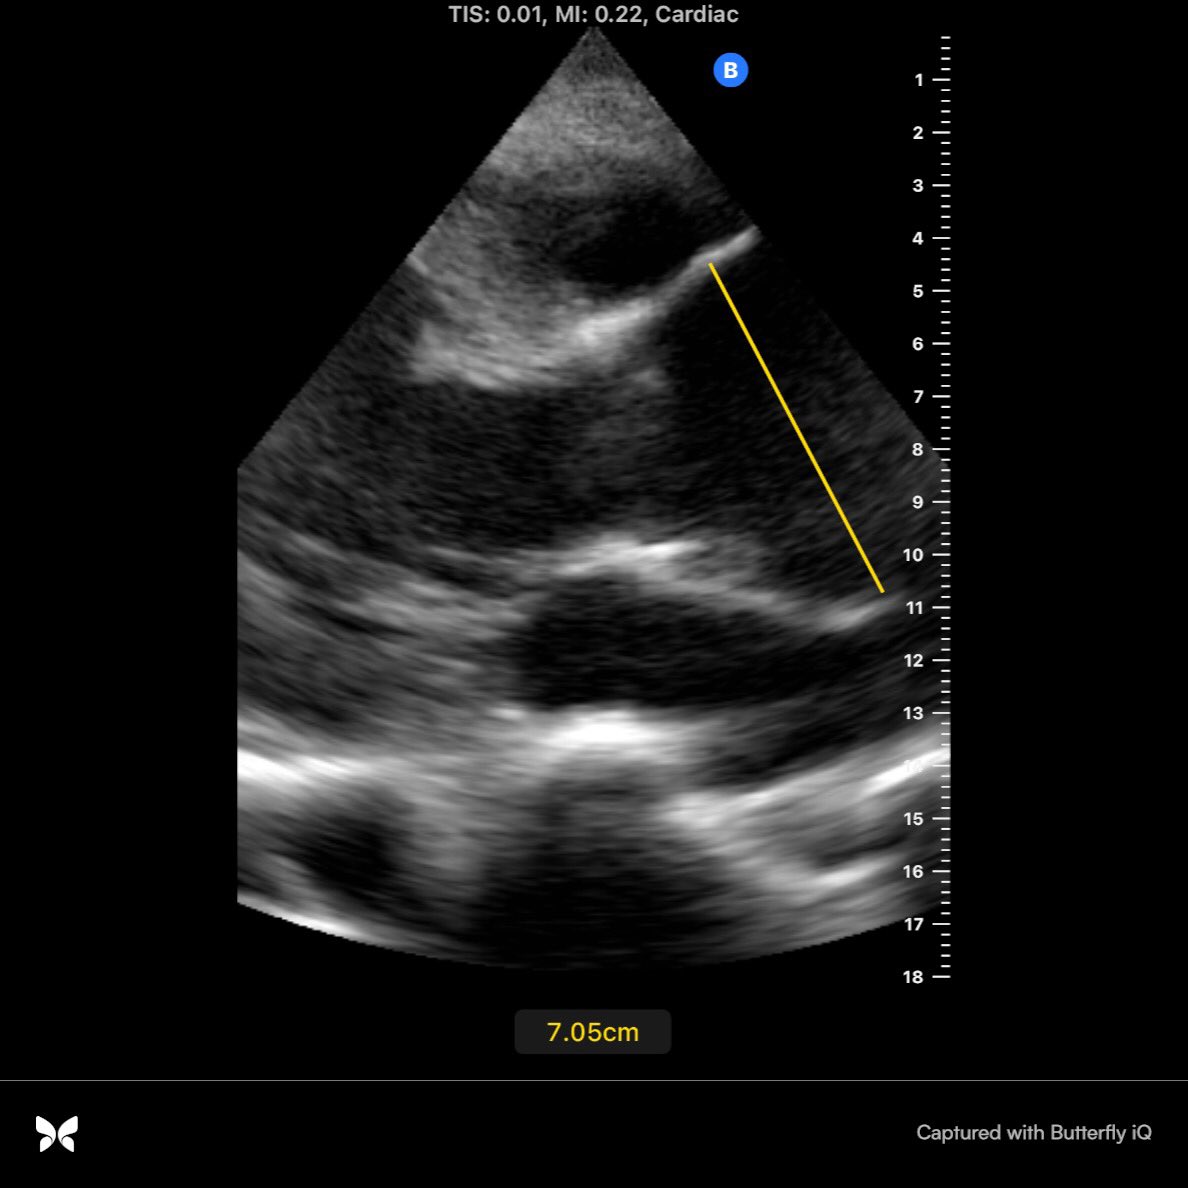

Bedside #pocus exam shown below:

Most glaring is the size of the aorta. It is clearly larger than the left atrium. Also notable is the anterior leaflet of the mitral valve isn’t opening much.

This is either due to mitral stenosis, systolic heart failure or aortic regurgitation. Placing color Doppler on the valve gives you the answer.

So in about 1-2 minutes we have a good idea what’s going on here: thoracic aortic aneurysm with severe aortic regurgitation. Measuring the aortic root and thoracic aorta confirms the diagnosis.